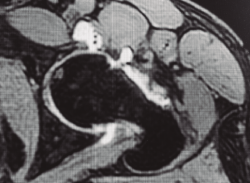

- Defectos capsulares: es importante en pacientes previamente intervenidos detectar en las artrorresonancias magnéticas (artro-RM) la existencia de defectos capsulares que, sumados a los previamente descritos, constituyen cada día con mayor claridad un criterio asociado a mala evolución clínica (Figura 2).

Figura 2. Paciente con geodas subcondrales acetabulares y en cabeza femoral, osteofito de contrachoque posteroinferior, espacios < 2 mm, incorrecta resección de CAM previo y defectos capsulares marcados.